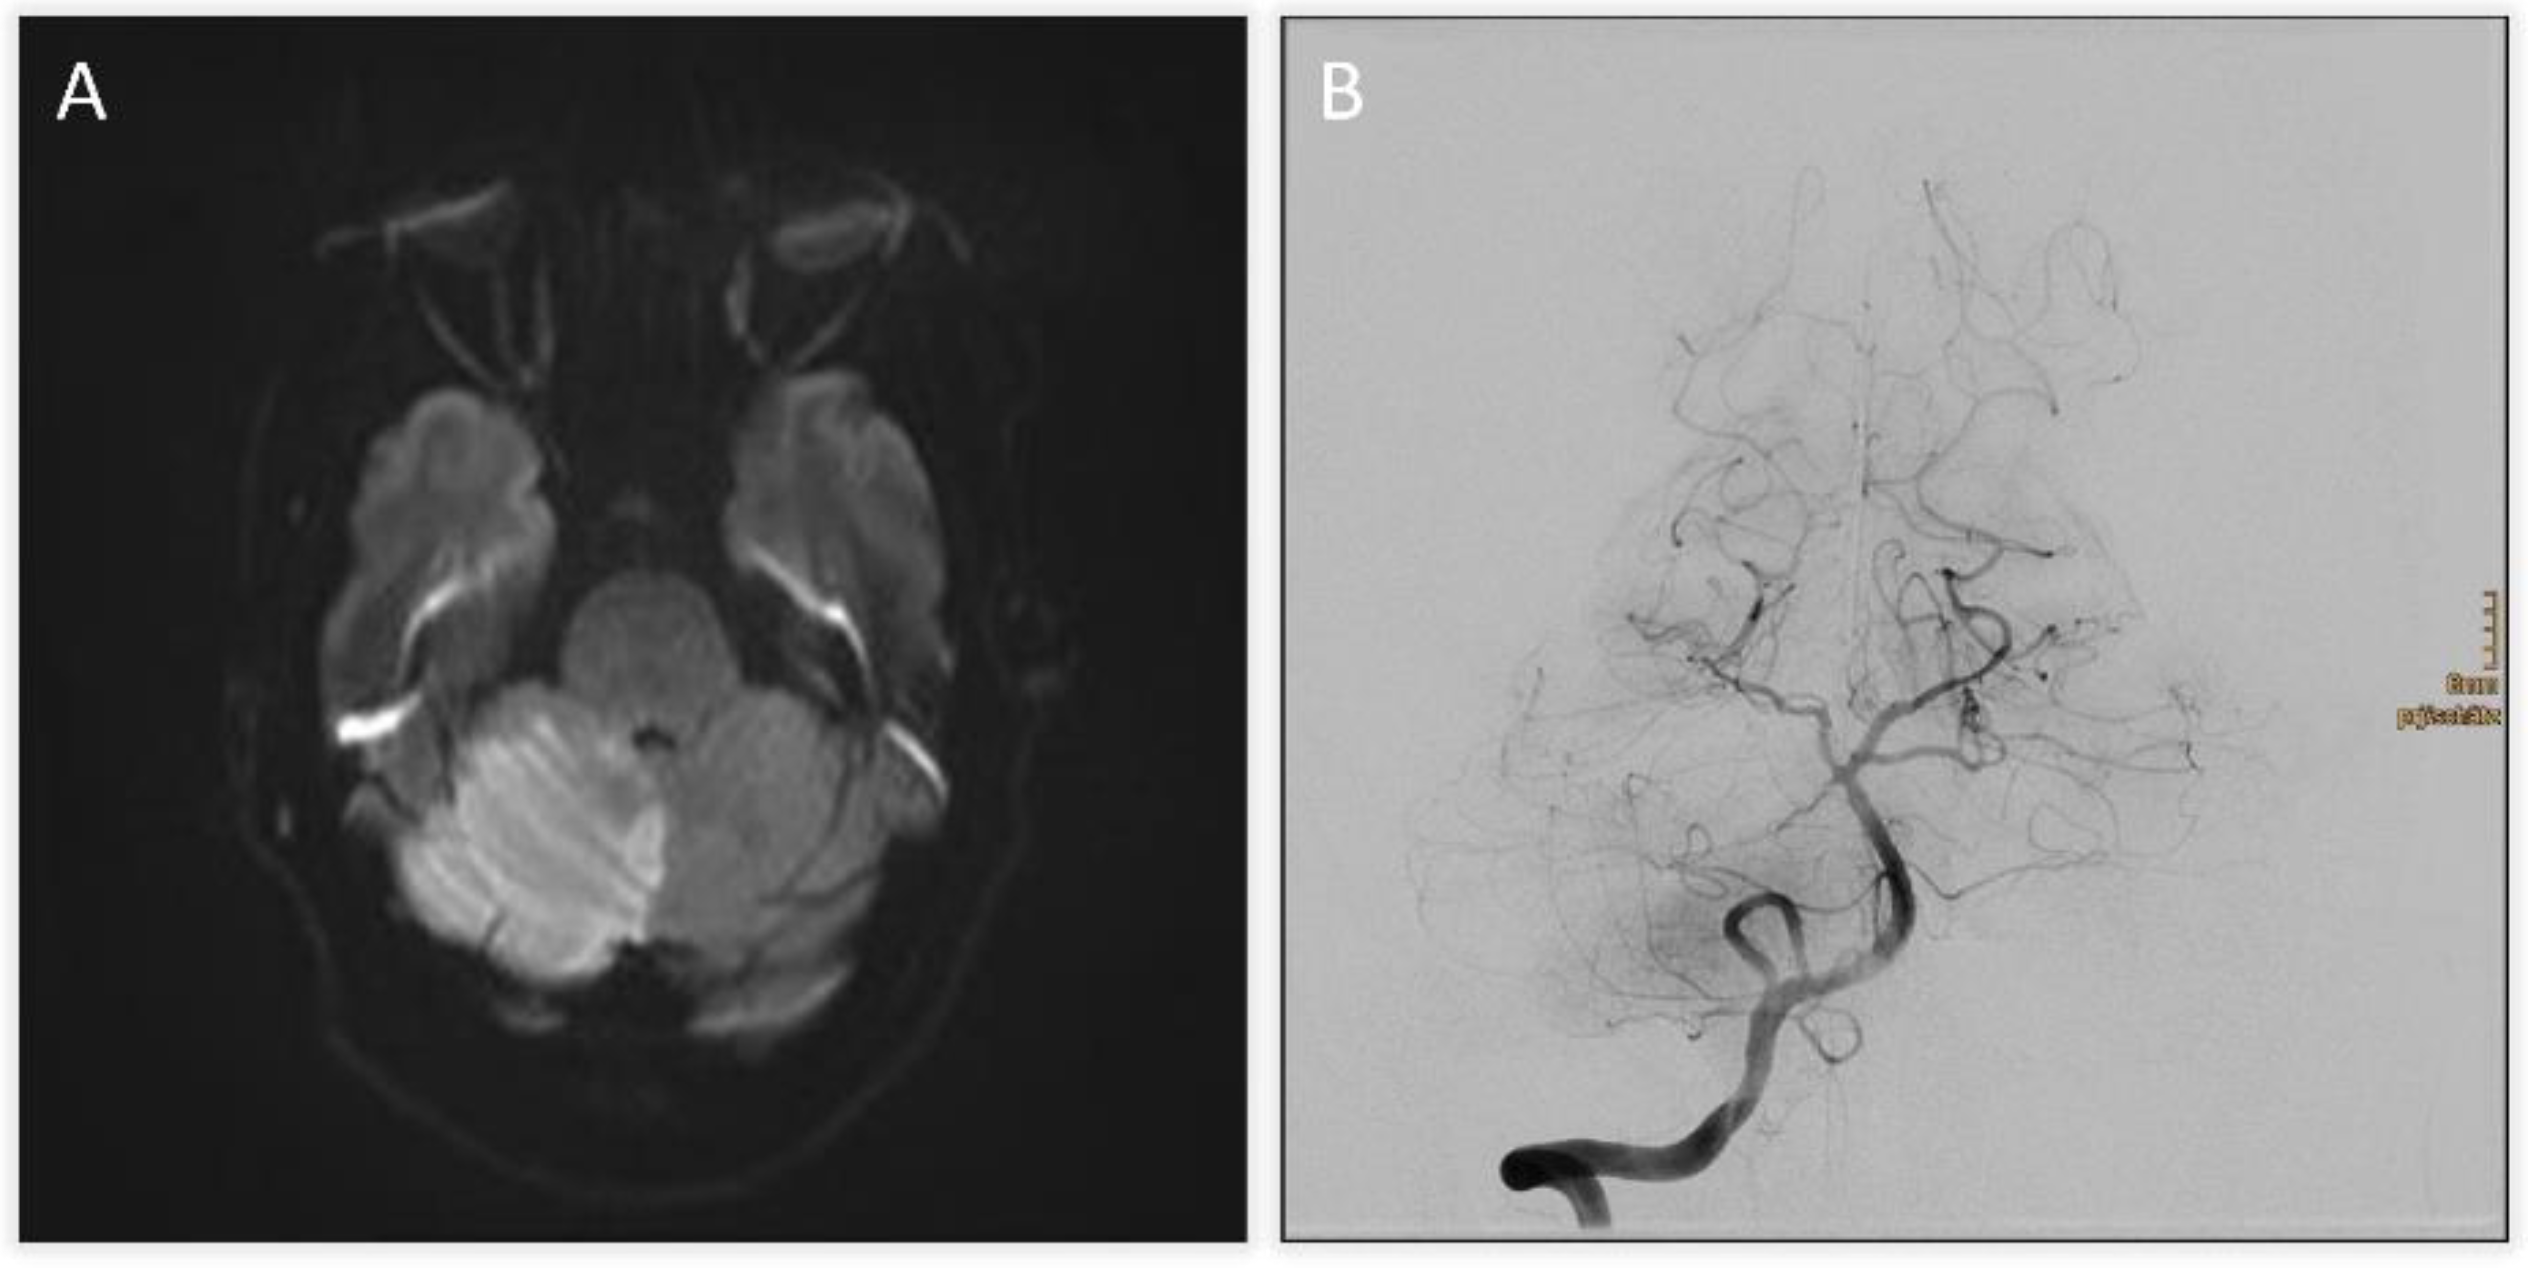

TOF-angiography identified a thrombus at the basilar tip. Intravenous thrombolysis was administered, followed by DSA confirming right SCA occlusion with preserved basilar patency (Figure 1B). Mechanical thrombectomy was attempted but unsuccessful. Follow-up CT revealed extensive hypodensity in the right cerebellum with mass effect and apparent extension into the brainstem, raising concern for infarction and poor prognosis (Figure 2A and Figure 2B). Immediate MRI, however, excluded brainstem infarction and confirmed predominantly reversible edema (Figure 2C). Emergency suboccipital decompression, partial resection of infracted parenchyma and ventricular drainage were performed (Figure 2D).

Figure 2. A and B) Follow-up CT revealing an expanding infarct of the right cerebellum with mass effect and apparent hypodensity in the pons, midbrain and diencephalon, raising suspicion of brainstem infarction. C) Axial diffusion weighted image obtained after suspicious CT findings excluding brainstem infarction and demonstrating predominantly cerebellar edema. D) Postoperative CT scan following suboccipital decompression, partial cerebellar tissue resection and ventricular drainage.